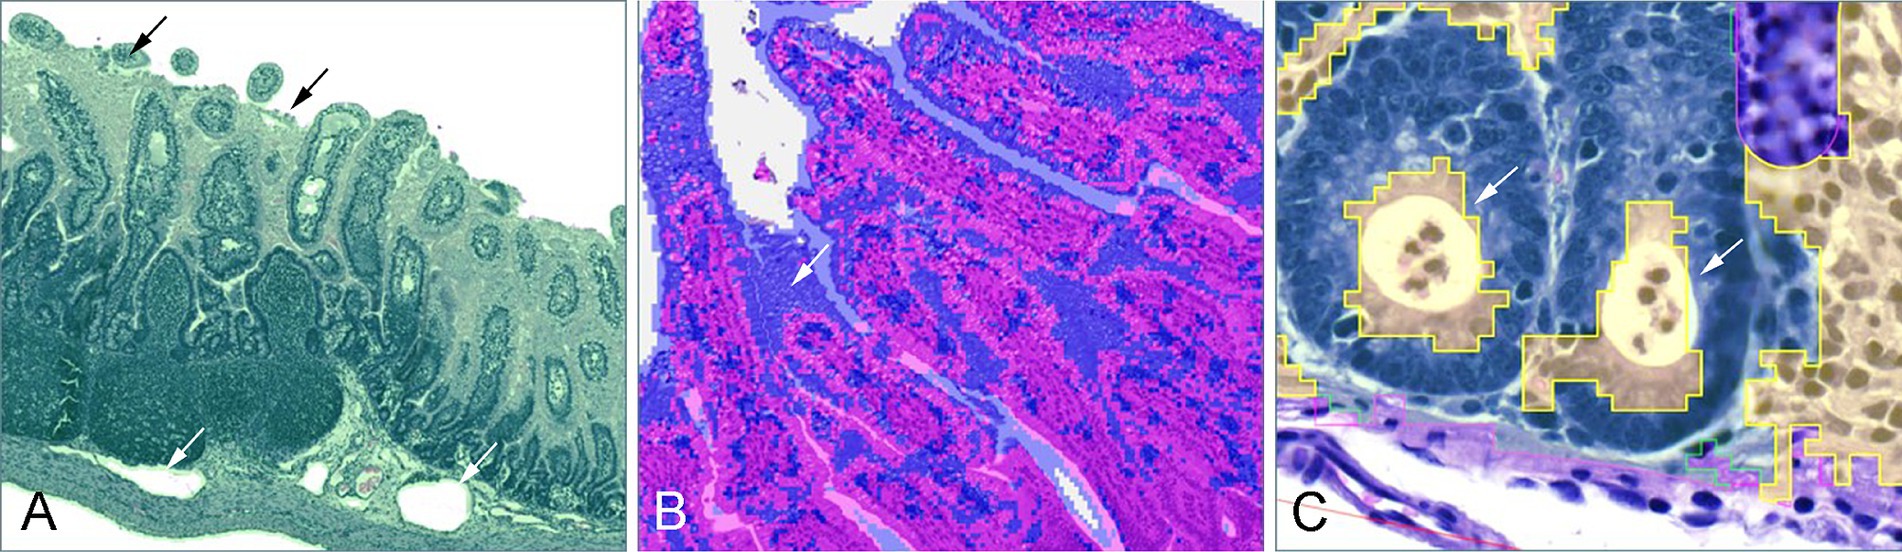

Figure 4. Frequently observed classification errors. (A) In step 1, luminal content and cellular debris was misclassified as part of the tissue (black arrows), and in cases of submucosal edema, dilated vessels were misinterpreted as part of the background (white arrow). (B) In step 2, fetal-type vacuolated epithelial cells on the villi of young piglets were often misclassified as part of the submucosa (white arrow). (C) In step 3, one of the commonly observed errors was the misclassification of crypt abscesses as part of the lamina propria (white arrows).

3.7 Step 2

In Step 2, the segmentation of the tissue into mucosa and submucosa relied on the training of a random trees algorithm. A predominant error was observed in younger piglets (4–21 days), where vacuolated fetal-type enterocytes in the epithelial lining were frequently misclassified as part of the submucosal tissues due to their distinct texture and fainter staining intensity (Figure 4B).

3.7.1 Step 3

In Step 3, pixel classification focused on differentiating the epithelial layer from the lamina propria, however, several recurring errors impacted model performance. Goblet cells, with their distinct cytoplasmic mucin stores and excentric, often not clearly visible nuclei, were occasionally misinterpreted as part of the lamina propria. Similarly, crypt abscesses, characterized by accumulations of cellular debris and neutrophilic granulocytes within crypt lumens, were often misclassified as lamina propria as well (Figure 4C). In younger piglets, the presence of fetal-type vacuolated epithelial cells, as seen in Step 2, contributed to a general overestimation of the lamina propria area by being incorrectly categorized as non-epithelial tissue. Conversely, in the age-balanced model, a notable underestimation of the lamina propria area was observed in piglets aged 25–67 days, where substantial portions of the lamina propria were misclassified as epithelial tissue, likely reflecting the model’s attempted adaptation to earlier developmental stages.